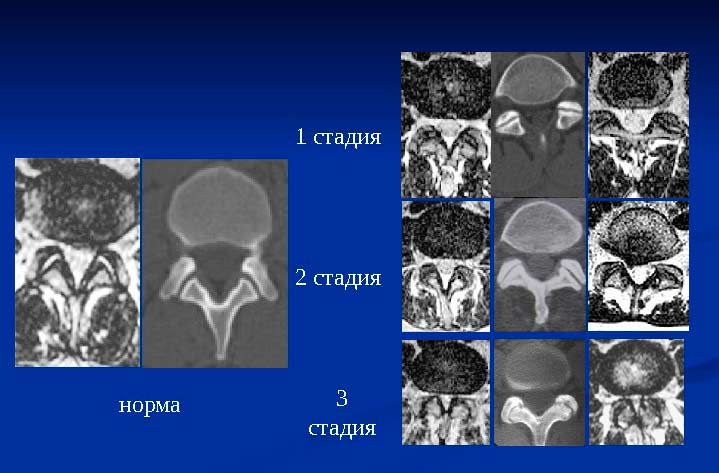

Спондилёз и его разновидность – спондилоартроз, как и остеохондроз, могут проявляться в разных отделах позвоночника. Эти болезни характеризуются стадийностью, поэтому клиническая картина разворачивается далеко не сразу, что мешает ранней диагностике заболеваний.

Важно! Стадийность определяется с помощью инструментальных методов. Критериями являются размер, характер нароста, высота межпозвоночного диска.

Таблица №1. Стадии заболеваний.

| Стадия | Описание |

| 1 стадия | На рентгенограмме можно увидеть много костных наростов, которые не покидают пределы позвонков. Межпозвоночные диски интактные. Их высота неизменна. |

| 2 стадия | Остеофиты выходят за пределы позвонков и срастаются. Но на второй стадии этот процесс остается незавершённым. |

| 3 стадия | Остеофиты полностью сращиваются и образуют скобки. Пораженный отдел позвоночника теряет свою подвижность. Наблюдается стеноз вертебрального канала. |